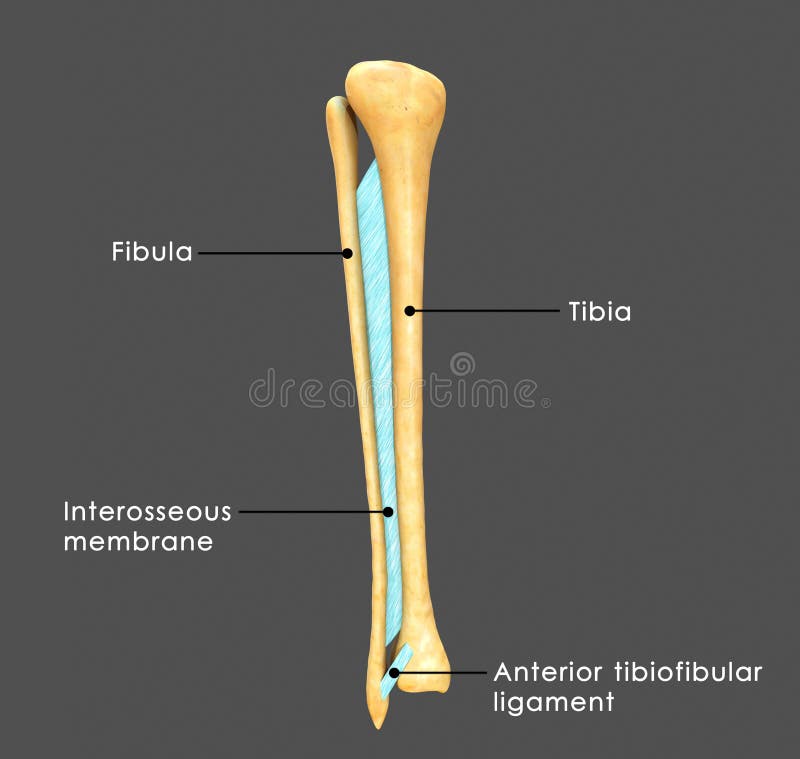

Tibiofibular Joints – Proximal – Distal – Interosseous Membrane …

Syndesmosis Between Fibula And Tibia Stock Illustration – Image: 46625341